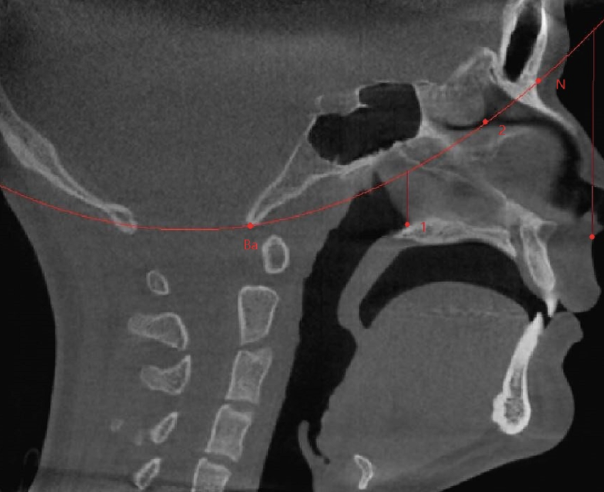

CBCT Airway Mapping

Proprietary 3D mapping of your unique airway architecture.

NightLase® Soft Palate Treatment — Full anatomical reveal.